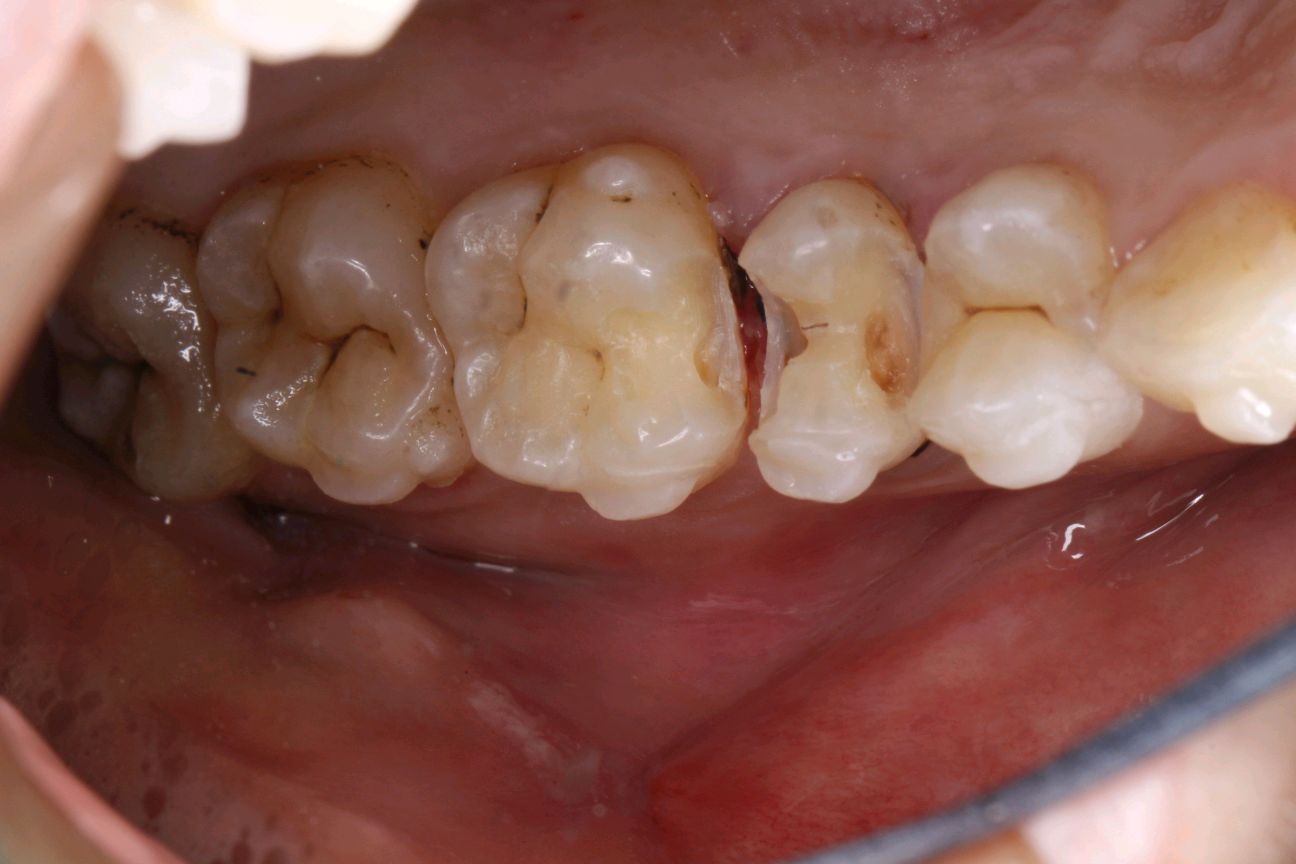

患者女,三十岁,15邻颌面大面积充填物,邻接过紧,食物嵌塞,探(+-),叩(-),冷测试正常,余无不适。很多人牙体缺损面积较大,补牙后很会出现脱落的现象,还有的让选择简单的修复模式补牙,但大量的临床研究显示,牙科树脂充填材料会产生聚合收缩(树脂材料老化),形成微渗漏,引起继发龋(顺着充填材料周围,在牙齿上出现新的腐坏、变黑)。像这种面积比较大的龋齿单纯补牙的话,不耐用。这时候就可以选择嵌体修复。嵌体牙体预备量少,能够保持牙齿外形的完整,减少对牙髓的刺激。还有就是嵌体更耐磨使用寿命较长,从而减轻了患者频繁补牙的痛苦。通过 CEREC 扫描更加精准有效的提高了我们工作效率,当天即可戴牙,正常使用。